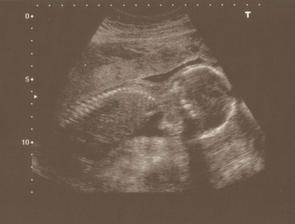

18.12.2008 první kontrola u lékaře.Vše v pořádku,na UTZ už bylo vidět srdíčko...Je 23.12.2008 a cítím,že přibírám.Vůbec nezvracím,jen je mi občas na omdlení a hodně spím...2.1.2009 Stále jsem hodně spavá a unavená.Občas je mi trochu špatně,ale nezvracím.Chutě mám různé,ale co opravdu vede-jsou polévky.Ty zbožňuju 🙂 Přibírám,ale zatím nejde poznat,že jsem těhotná...9.1.kontrola,miminko je 2,6 cm velké,fotka z ultrazvuku se doktorovi moc nepovedla,ale na monitoru už to začínalo vypadat jako človíček 🙂Dostala jsem těhotenskou průkazku,dle UTZ jsem 9+3,termín porodu 11.8.2009.Sestřička mi pak brala krev,měřila tlak-ten mám bohužel hraniční (140/85).Stále bývám unavená,často mě opravdu hodně bolí nohy,ale jinak je mi dobře...14.1.Mám za sebou EKG...2.2.jsme byli v Olomouci na genetice.Miminko bylo na UTZ moc nádherné.Krásně mu tlouklo srdíčko.Brali mi také krev.Zatím to vypadá,že se vše vyvíjí tak,jak má.Jsem moc šťastná.Poprvé byl se mnou na UTZ i přítel,bylo to úžasné...Kontrola u obvodní lékařky mě uklidnila.Vysoký tlak nemám.Přesněji,jsem z měření nervozní a tím se zkreslují výsledky...Po nemoci jsem něco zhubla,takže v 15.týdnu jsem zatím 2kg v plusu.Hodně mi porostly prsa.To je daleko znatelnější než bříško-zatím 🙂 ...13.2.jsem byla v poradně.Doktor už měl výsledky z genetiky,které dopadly výborně.Další kontrolu mám za měsíc...Tento týden jsem začala číst miminku.Vybrala jsem si Kroniku města Kocourkova.Bavím se tím i já.Každý večer jednu kapitolku.Doufám,že miminko cítí,že se na něj moc těšíme....20.2. jsem ucítila první pohyby.Překvapilo mě to moc.Byla jsem teprve v 15tt+3.A čekám první mimi.Bylo to velmi jemné,jako by mi tam proplula rybička,takové zašimrání...Hrozně zvláštní.Ležela jsem a měla přitisklou dlaň na bříšku a najednou-jakoby se mi něco vevnitř otřelo o stěnu.Zatím to jinak výrazně necítím.Už vůbec ne během činnosti a není to žádné kopnutí....13.3.jsem byla na další kontrole.Miminko uvidíme na velkém ultrazvuku 24.3.Jsme moc napjatí,protože si chceme nechat říct pohlaví....Taky jsem stihla kontrolu u zubařky.Naštěstí vše v pohodě-jako před těhu 🙂 ...21.3. přes pupík mám 97 cm 🙂...24.3.byli jsme s přítelem na velkém ultrazvuku.Miminko má 20 cm a váží 350 g.Vrtělo hlavičkou a dokonce si i zívlo 🙂Doktor všechno možné poměřil,zkontroloval,ukázal.Dokonce si tipl pohlaví mimouška.Ale víme to jen my s přítelem a tak to zůstane až do porodu-překvapení pro ostatní 🙂 Máme 15 min. záznam na DVD...30.3. podrobné interní vyšetření-zjištěn možný syndrom bílého pláště 🙂....

31.3.kontrola srdíčka miminka-vše vypadá v pořádku....11.4.konečně i můj přítel ucítil jemné "klop-klop" 🙂 přesně ve 22+4tt.Já už cítila toto kopkání asi 2 týdny.Dříve to bylo jen jako proplutí rybičky 🙂 ....5.5. test na těhotenskou cukrovku.Výsledky jsou v pořádku-jupíííí!...15.5.Kontrola v poradně-zatím dobrý 🙂...28.5.Zdá se mi,že miminko více a častěji kope...5.6.Mimuško má dle ultrazvuku přibližně 35 cm a 1700 g.Všechno je v pohodě.Dokonce i krevní tlak mám vzorový-120/80 🙂) ...16.6.bříško poskočilo na 109 cm....22.6.máme pořízeno 99% věcí do výbavičky.Teď máme ještě 50 dní do termínu.Takže v klídku si můžu vše vyprat,vyžehlit a srovnat věcičky do regálků...Na kontroly chodím čím dál častěji...13.7.jsme se byli podívat do porodnice.Prostředí bylo velmi pěkné.Jen jsem byla překvapená,že kromě noční košile,si budu muset vzít naprosto vše vlastní.To,abych si nabalila několik lodních kufrů :-O ...24.7. - 37+3 tt.-kontrola u lékaře-srdíčko miminka tlouklo jako stádo koní 🙂 Miminko je,zdá se,spokojené a zdravé.Hlavičku má uloženou dole,tak snad už nedostane nápad v bříšku kdovíjak cestovat.Niic nenasvědčuje tomu,že by se porod blížil.A přitom jsem už umyla všechna okna,vyprala a pověsila záclony,zkouším kdejaké babské rady...Vypadá to,že si miminko v bříšku náramně užívá 🙂) ...31.7. - 38+3 tt. mimi se stále nechystá ven.Odhadem má asi 3000 g....4.8. přes pupík mám 112 cm....6.8.poslední kontrola u mého gynekologa.Hlavička miminka je už sestouplá,ale jinak se ven nijak nehrne 🙂 ...11.8.kontrola v porodnici,miminko má odhadem 3300g a pořád nemá zájem vylézt ven.(od minulé odhadní váhy přibírá denně asi 30g)...K velkému překvapení se cosi začalo dít ještě večer v den termínu-to jsem ještě netušila,že je to začínající porod 🙂 ...Až na druhý den 12.8. po poledni mě napadlo,že to budou asi poslíčky.K večeru jsem si,ale raději začla měřit stahy:17.14,17.17,17.20-za pár minutek mi lupla voda a bylo to celkem jasné 🙂) Před 18.h jsme se tedy vydali na výlet do porodnice.A ve 20.45 h jsem už držela Terinku v náručí.Přišla na svět v příjemné atmosféře provoněné vůní z aromalampy a při hudbě Mobyho...16.8.pustili nás z porodnice domů.